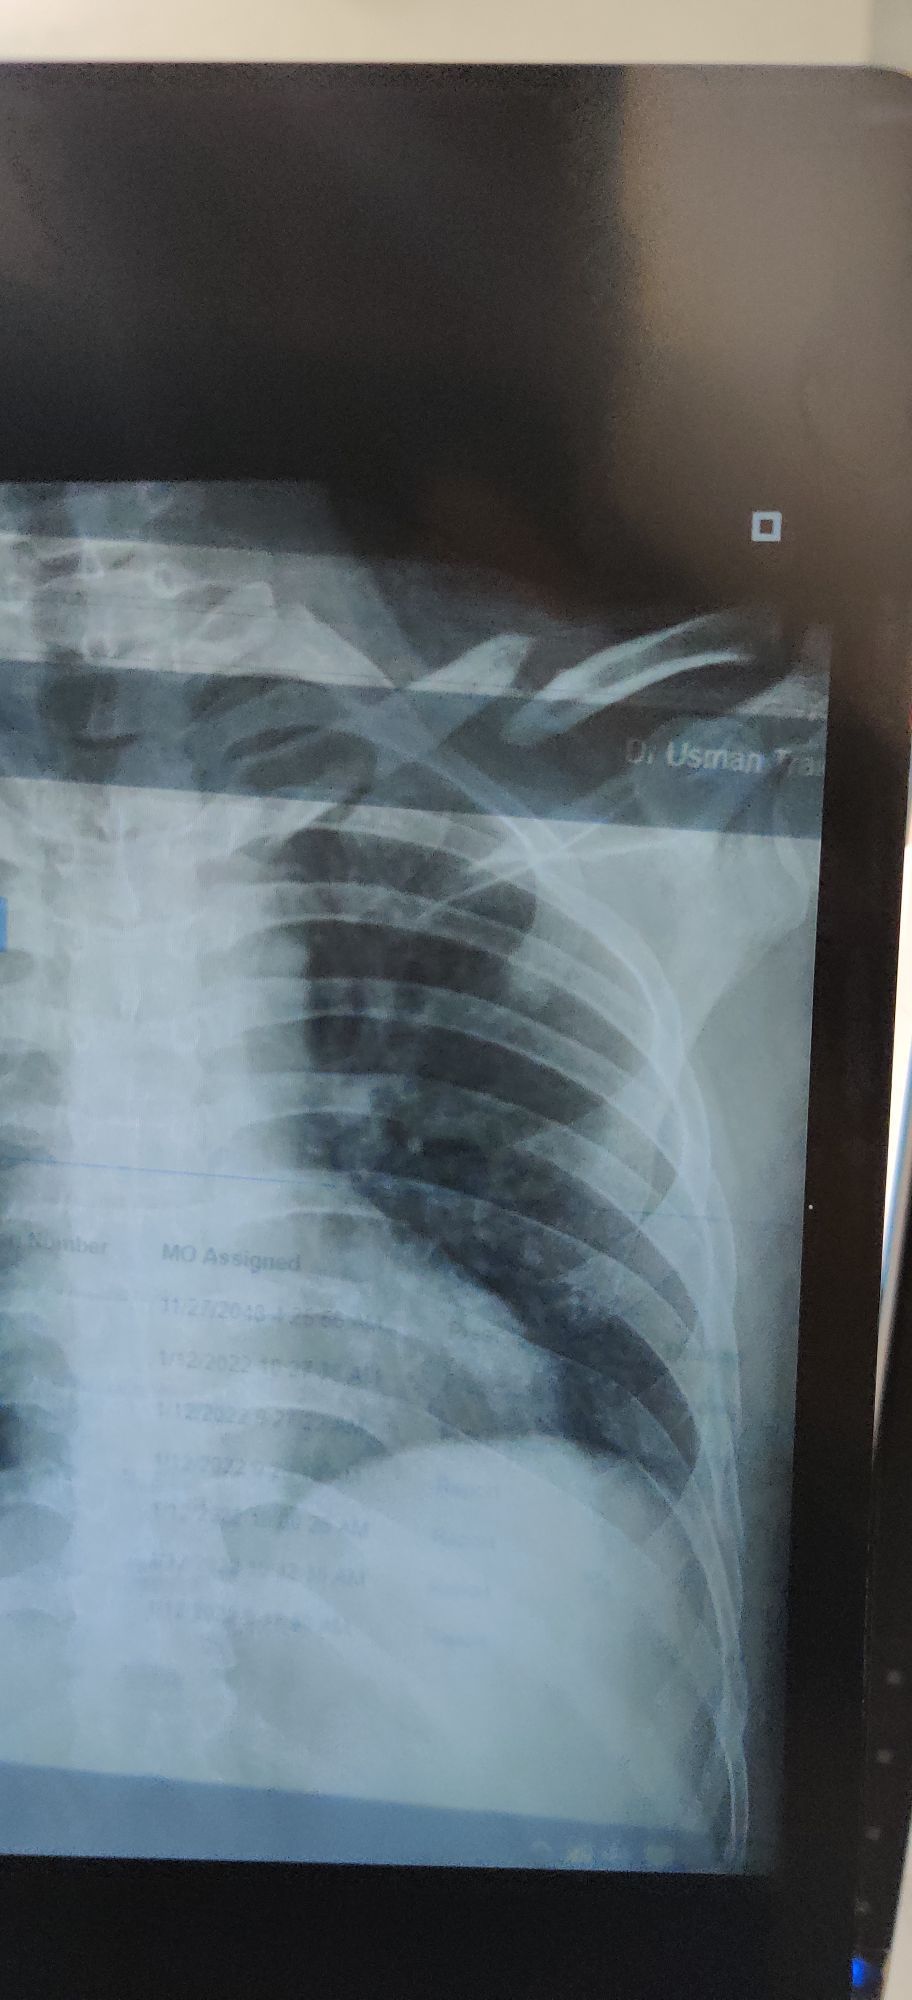

Dr Usman

Clavicle Fracture

Fracture

Rta

Clavicle